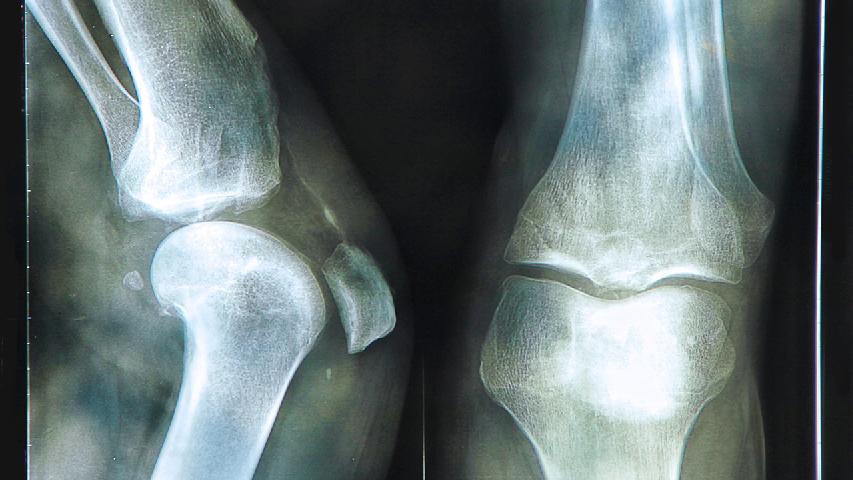

人的骨节有问题还是要引起注意了,而积极了解这些我们大家要做好了解,特别是出现了类风湿会存在麻烦的,所以多来了解这些以后也是要采取好的办法来及时进行检查较为合适,那么类风湿关节炎的检查方法有哪些呢?下面我们就来一起了解一下吧。1、滑液检查,类风湿关节炎患者的滑液外观呈混浊的草黄色浆液,粘稠度降低,粘蛋白凝固不全,可见到类风湿关节炎细胞。这也是类风湿关节炎的检查...

专家指出,类风湿性关节炎并不是不治之症,只要抓住治疗好时机,选择好方法,可以通过很多治疗途经痊愈的,那么,类风湿性关节炎检查方法有哪些呢?相信这是很多患者都想要了解的问题,下面我们就来一起看看下文的详细介绍吧,相信对大家会有所帮助的。1.血细胞沉降率大多数患者血细胞沉降率增快,尤其是在急性期。2.血红蛋白含量略低于正常,晚期病例则可出现轻度贫血,血红蛋白含量...

说到关节炎疾病,患者一定对关节炎的一些常识问题都有所了解了,比如关节炎的检查,就是关节炎患者不得不去面对的一个问题,检查出了实际的病情症状,才能够做到对症治疗,不延误病情,但是有很多患者对此并不是很了解,那么膝盖关节炎怎么检查?下面我们就来一起了解一下吧。在早期,类风湿性关节炎缺乏特异性的具有诊断价值的X线特点。但是,如果把各种症状和体征、好发部位、实验室检...